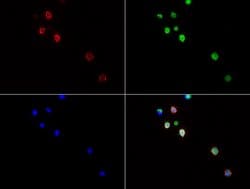

CD3 epsilon is part of the CD3 subunit complex which is crucial in transducing antigen-recognition signals into the cytoplasm of T cells and in regulating the cell surface expression of the TCR complex. T cell activation through the antigen receptor (TCR) involves the cytoplasmic tails of the CD3 subunits CD3 gamma, CD3 delta, CD3 epsilon and CD3 zeta. These CD3 subunits are structurally related members of the immunoglobulins super family encoded by closely linked genes on human chromosome 11. The CD3 components have long cytoplasmic tails that associate with cytoplasmic signal transduction molecules and this association is mediated at least in part by a double tyrosine-based motif present in a single copy in the CD3 subunits. CD3 may play a role in TCR-induced growth arrest, cell survival and proliferation. The CD3 antigen is present on 68-82% of normal peripheral blood lymphocytes, 65-85% of thymocytes and Purkinje cells in the cerebellum. It is never expressed on B or NK cells. Decreased percentages of T lymphocytes may be observed in some autoimmune diseases. The genes encoding the CD3 epsilon, gamma and delta polypeptides are located on chromosome 11. Defects in this gene are associated with T cell immunodeficiency and has been linked to Type 1 Diabetes deficiency in women.Specifications

| Immunocytochemistry, Immunofluorescence, Immunohistochemistry (Paraffin) | |